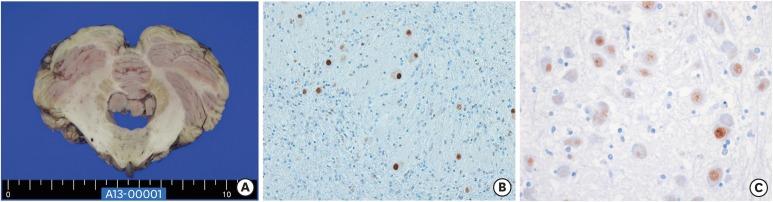

Dentatorubropallidoluysian atrophy (DRPLA) is a neurodegenerative disease caused by an expansion of a cytosine-adenine-guanine (CAG) repeat encoding a polyglutamine tract in the atrophin-1 protein. Unlike other CAG repeat diseases, sleep related problems have not been reported in patients with DRPLA. There was a 65-year-old man and his family with DRPLA. They suffered from seizure, gait disturbance, and cognitive decline. The patients commonly showed dream enacting sleep disorder, insomnia. The results from overnight polysomnography showed rapid eye movement (REM) without atonia in patients with DRPLA. The man died 2 years after diagnosis and was subjected for brain autopsy. We report REM sleep behavior disorders in patients with DRPLA confirmed with polysomnography with pathological description of the patient.

摘要

齿状核红核苍白球路易体萎缩症(DRPLA)是一种由抗萎缩蛋白 1 蛋白中编码多聚谷氨酰胺链的胞嘧啶-腺嘌呤-鸟嘌呤(CAG)重复扩增引起的神经退行性疾病。与其他 CAG 重复疾病不同,DRPLA 患者没有报告与睡眠相关的问题。本文报道了一例 65 岁男性及其家族的 DRPLA 病例。他们患有癫痫、步态障碍和认知能力下降。患者通常表现出梦动睡眠障碍和失眠。整夜多导睡眠图的结果显示,DRPLA 患者的快速眼动(REM)期间无动性。该患者在诊断后 2 年死亡,并接受了尸检。我们通过多导睡眠图检查并结合患者的病理描述,证实了 DRPLA 患者存在 REM 睡眠行为障碍。

Pathological accumulation of atrophin-1 in dentatorubralpallidoluysian atrophy.齿状核红核苍白球路易体萎缩症中萎缩素-1的病理性积聚。

Int J Clin Exp Pathol. 2011 Apr;4(4):378-84. Epub 2011 Apr 25.